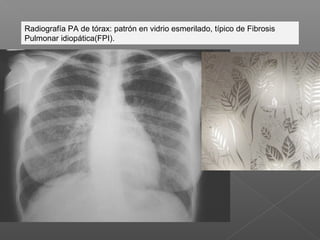

Radiografía PA de tórax: patrón en vidrio esmerilado, típico de Fibrosis

Pulmonar idiopática(FPI).